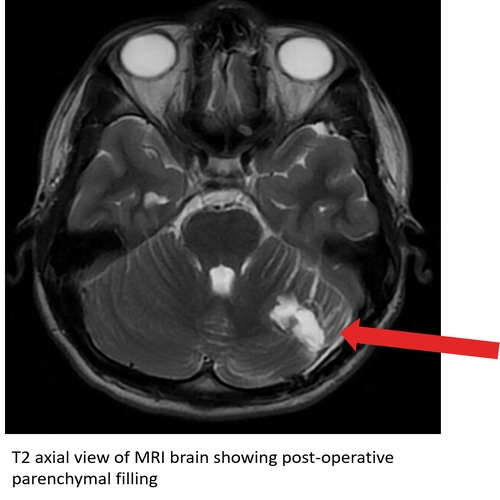

At the time of discharge, he was ambulating without assistance, though with some subjective dizziness. He began balance training at 2 weeks post-op and was able to return to light aerobics and weight training by 4 weeks. A repeat MRI at 6 weeks revealed no residual tumor along with appropriate parenchymal filling of the cerebellar defect. Case Photo #3 Case Photo #4 He was able to progress his aerobic activity at 8 weeks. He received full clearance to return to practice and full weight training at 12 weeks. By 16 weeks, he had a full return to sport. A repeat MRI performed 6 months post-op revealed further parenchymal filling of the defect and no new masses.